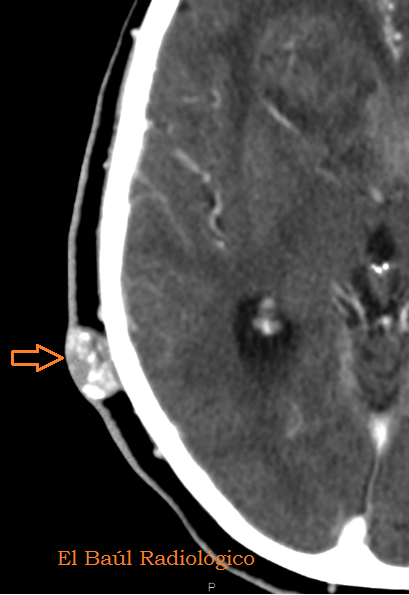

FIGURA 3) Imagen magnificada de los dos quistes, donde se aprecia su dependendencia del cuero cabelludo.

(Magnified imageof the twocystswhichshowsits dependence on thescalp)

FIGURA 4) Otro quiste sebáceo, totalmente calcificado. Es redondo y está separado de la tabla externa del cráneo, característica que le distingue de un osteoma frontal.

(Anothersebaceous cyst, rounded and fullycalcified.It is separated fromthe outer tableof the skull, a feature that distinguishes itfrom afrontalosteoma)